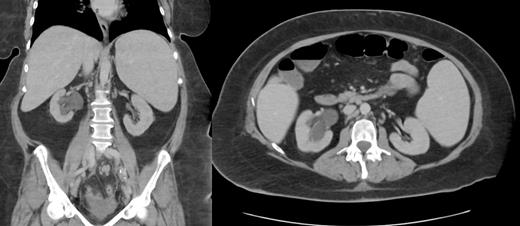

Case Description: We present a rare and intriguing case of a 51-year-old female admitted for acute on chronic microcytic anemia, with accompanying symptoms of decreased oral intake due to nausea, and vomiting, significant weight loss, night sweats, and lower quadrant abdominal pain. Additionally, she reported decreased urinary frequency, urgency. CT imaging of the abdomen and pelvis revealed a large soft tissue mass measuring 7.6 x 4.6 x 5.7 cm in the posterior right pelvic region, resulting in severe hydroureteronephrosis, along with bilateral iliac chain adenopathy, retroperitoneal lymph node enlargement, and severe splenomegaly. CT chest revealed several small lung nodules indicating distant metastasis. Additionally, the patient exhibited elevated levels of LDH, CA 199, and CRP, and decreased hemoglobin levels, indicating the presence of systemic disease. A CT-guided biopsy of the right pelvic mass confirmed the diagnosis of non-Hodgkin malignant lymphoma, specifically of the diffuse large B-cell type. Immunohistochemistry and flow cytometry demonstrated CD20 positivity in the proliferating large cells, consistent with DLBCL, and revealed a kappa-restricted B-cell population expressing CD19, CD20, and kappa surface immunoglobulin light chains. The PET scan showed prominent splenomegaly, adenopathy, and retroperitoneal involvement, corroborating the lymphoma diagnosis. The patient was discharged for outpatient follow-up with oncology with a treatment plan of R-CHOP (rituximab, cyclophosphamide, doxorubicin, vincristine, and prednisone) administered every 3 weeks, omitting rituximab during the first cycle.

Discussion: This case stands out due to the unusual presentation of a large DLBCL in the pelvic region, which is a relatively rare occurrence. The localization of DLBCL in the pelvis poses a diagnostic challenge, as symptoms may overlap with various other conditions. Moreover, the extensive involvement of the retroperitoneal lymph nodes and splenomegaly added complexity to the management of the disease. The rarity of DLBCL in the pelvis highlights the importance of considering lymphoma in the differential diagnosis of patients presenting with non-specific pelvic symptoms and acute anemia. Early recognition of such cases is crucial for timely intervention and optimal treatment planning. Understanding the immunophenotypic characteristics of the tumor is essential for tailoring effective therapeutic strategies. This unique case sheds light on the need for further research and evidence-based guidelines for managing NHL in uncommon anatomical locations, promoting better patient outcomes and quality of life.